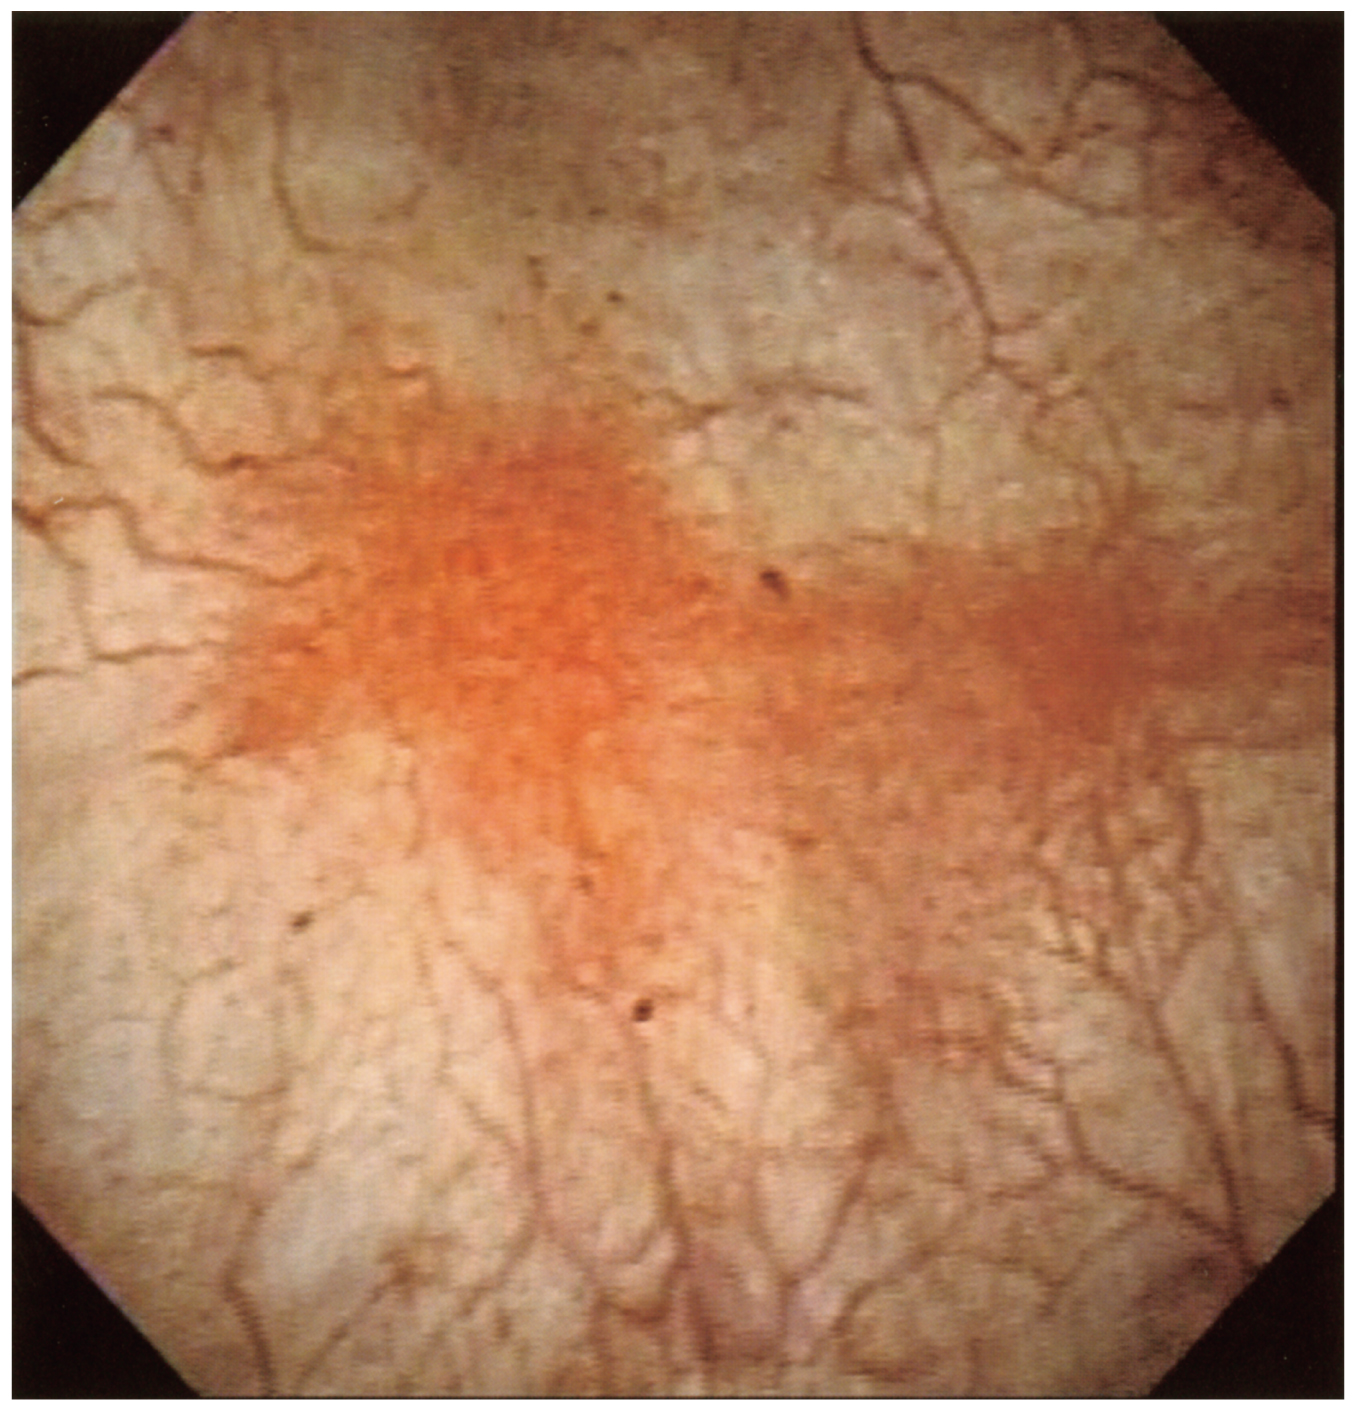

45歳の女性。6か月前からの下腹部痛と頻尿を主訴に来院した。下腹部痛は尿が膀胱に溜まってくると悪化し,排尿後には疼痛の改善がみられる。排尿回数は,20~25回/日であった。尿細胞診は陰性。膀胱鏡像を下に示す。